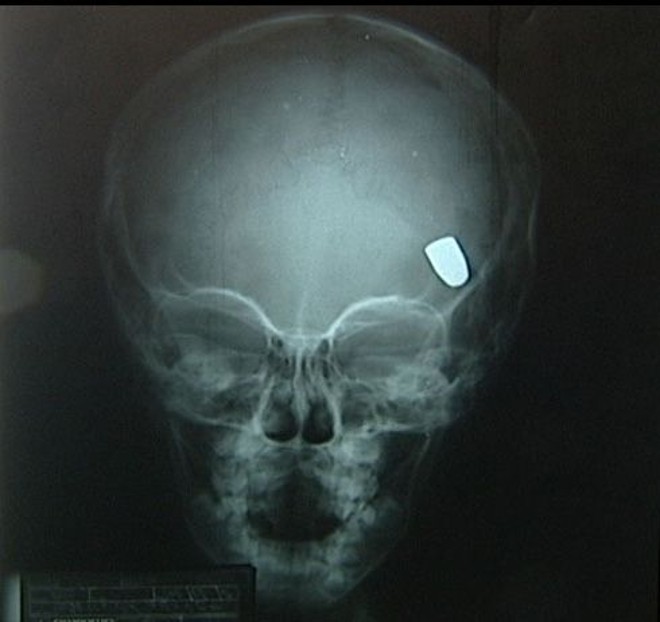

A tia de Samuel, Divalcir Oliveira, contou que a médica não quis dar pontos no ferimento, pois segundo ela, o procedimento deveria ter sido feito no primeiro dia. Como o menino não melhorou, a família pagou por um raio X. A radiografia mostrou a bala dentro da cabeça de Samuel.

O neurocirugião que atendeu a criança ficou impressionado com o raio X. Samuel já saiu da UTI e segundo o médico não deve ter sequelas.